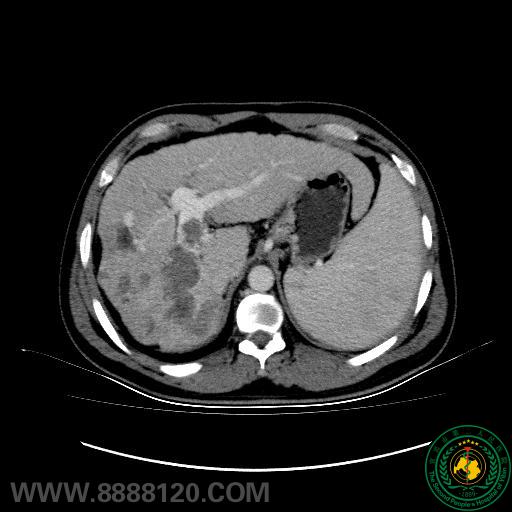

影像科介入室肝癌介入治疗取得新进展

影像科介入室肝癌介入治疗取得新进展2916